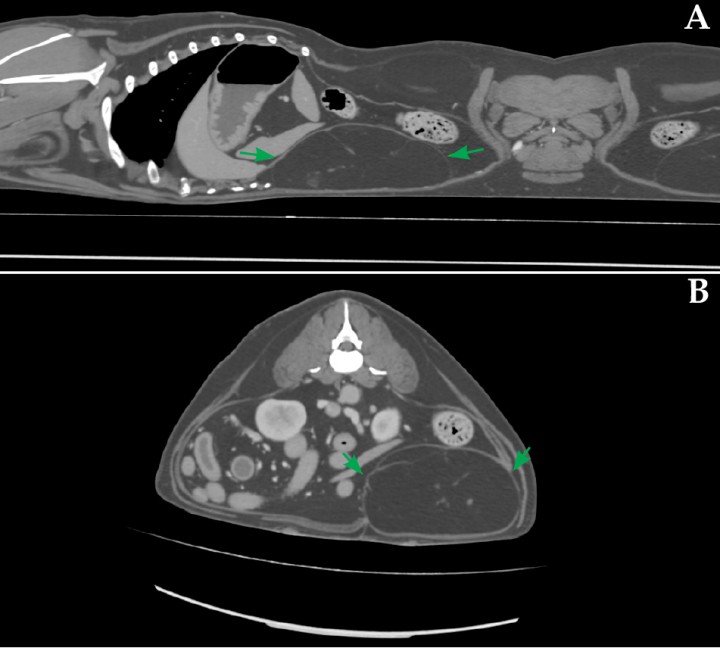

En cirugía abdominal se ha descrito el empleo de técnicas neuroaxiales, como la anestesia epidural, y de bloqueos fasciales, tales como el del plano del cuadrado lumbar, el bloqueo paravertebral torácico, el bloqueo del plano transverso del abdomen y el bloqueo del plano erector espinal. En este caso se realizó un bloqueo guiado por ecografía (Mindray M9 Vet, Mindray Bio-Medical Electronics Co., China) del plano dorsal del cuadrado lumbar (D-QLP) 20 minutos antes de comenzar el procedimiento quirúrgico. Para ello, con el paciente en decúbito lateral y el transductor (14-6 MHz, L14 – 6Ns, Mindray Bio-Medical Electronics Co., Shenzhen, China) posicionado caudal y paralelo a la última costilla y el marcador orientado dorsalmente, se avanzó una aguja espinal (22 G y 63 mm) siguiendo una dirección ventrodorsal mediante una técnica “in plane”, hasta situar la punta de esta en el plano comprendido entre el cuerpo vertebral de L1, su proceso transverso y el aspecto dorsal del músculo cuadrado lumbar. El bloqueo se realizó de forma bilateral inyectando 0,5 mL/kg de bupivacaína al 0,25 % (Bupivacaina B. Braun, B. Braun, Melsungen) a nivel de L1 (Figs. 3 y 4).

<p>Imagen ecográfica de la aguja con la punta posicionada en el plano dorsal del músculo cuadrado lumbar, adyacente al cuerpo vertebral y proceso transverso de L1. CL: cuadrado lumbar; CV: cuerpo vertebral; D: dorsal; EE: erector espinal; FT: fascia transversal; FTL: fascia toracolumbar; L: lateral; M: medial; OE: oblicuo externo; OI: oblicuo interno; PA: punta de la aguja; PM: psoas menor; PT: proceso transversal; V: ventral.</p>

Figura 4

Imagen ecográfica de la aguja con la punta posicionada en el plano dorsal del músculo cuadrado lumbar, adyacente al cuerpo vertebral y proceso transverso de L1. CL: cuadrado lumbar; CV: cuerpo vertebral; D: dorsal; EE: erector espinal; FT: fascia transversal; FTL: fascia toracolumbar; L: lateral; M: medial; OE: oblicuo externo; OI: oblicuo interno; PA: punta de la aguja; PM: psoas menor; PT: proceso transversal; V: ventral.